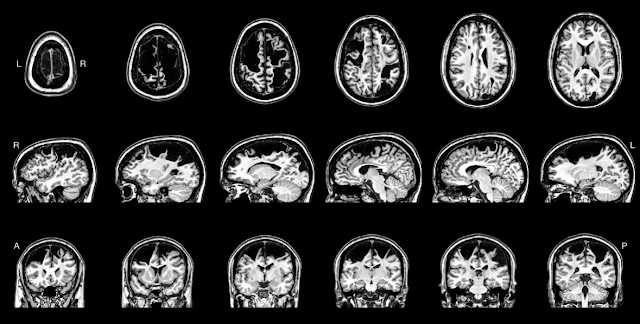

Ripartiamo dall’ortopedico che vede Leonard tredicenne, ipotizza una neuropatia ulnare e prescrive la fisioterapia ma invia a un neurologo per un’ulteriore valutazione. Il neurologo, in base ai risultati dell’esame obiettivo, prescrive una risonanza magnetica, che mostra un reperto inatteso: un’estesa lesione bilaterale compatibile con infarti cerebrali perinatali.

Leonard viene seguito nei due anni successivi dagli specialisti della clinica neurologica dell’ospedale pediatrico di Saint Louis nel Missouri, Stati Uniti, che, in collaborazione con altri reparti, conducono uno studio neuroanatomico e neuropsicologico approfondito nell’intento di rintracciare le possibili spiegazioni di come sia avvenuto che una lesione così estesa, che ha ridotto il volume cerebrale degli emisferi di circa 259 cm3, corrispondenti a circa il 20%, abbia lasciato inaspettatamente esiti così lievi.

Alla RM, presentata nell’articolo, viene documentato che “l’emisfero sinistro ha subito una perdita estesa della corteccia frontale, inclusa la perdita quasi totale del solco centrale e del giro precentrale, nonché nel giro frontale medio e superiore. La perdita corticale a destra è ancora più estesa e coinvolge sia la corteccia frontale che quella parietale, ma con notevole risparmio della circonvoluzione pre- e post-centrale inferiore”.

Attraverso l’applicazione di procedure innovative di risonanza magnetica funzionale (fMRI) e con tensore di diffusione (DTI), Laumann e collaboratori hanno realizzato una mappatura funzionale di precisione che dimostra gli effetti dei diversi processi di plasticità innescati dopo la lesione.

Nelle regioni sottocorticali e cerebellari, i movimenti della mano hanno mostrato un’attivazione tipica. Nella corteccia interessata dalle lesioni, le risposte ai compiti motori della mano destra hanno mostrato un’attivazione del giro post-centrale dell'emisfero sinistro e quindi una rimappatura posteriore della funzione motoria. Le risposte ai compiti motori della mano sinistra sono intatte, ma limitate alla piccola porzione preservata della corteccia motoria dell'emisfero destro.

Pertanto, la rappresentazione motoria della mano sinistra di Leonard si è mantenuta integra ma concentrata in un territorio notevolmente più ristretto del solco centrale destro. Questo processo ha garantito le normali funzioni motorie della mano sinistra. Al contrario, la rappresentazione motoria della mano destra pur occupando un territorio corticale più esteso, spostato posteriormente al giro post-centrale in seguito alla completa perdita del giro precentrale, è funzionalmente compromessa.